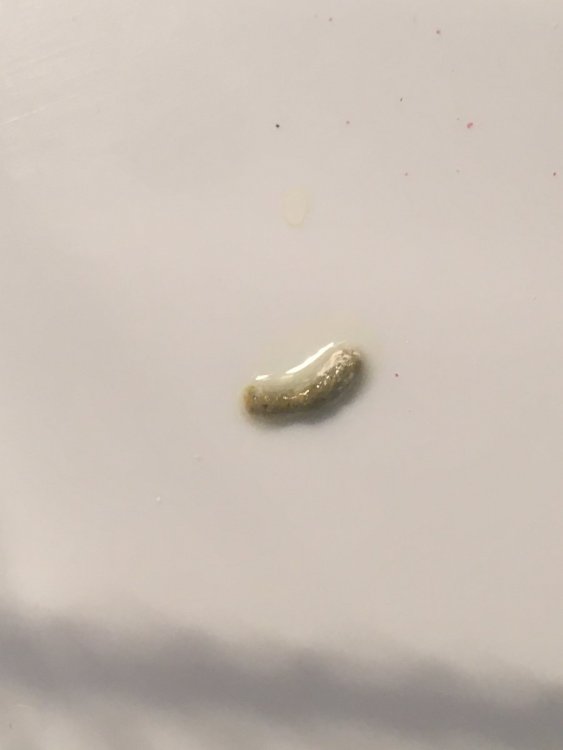

Здравствуйте, помогите, пожалуйста. Орнитолога у нас поблизости нет, ветеринары разводят руками и помочь не могут, не понимают они в птицах. у нас болеет самка волнистого попугая. Взяли её ещё летом, была совсем маленькая. Много спала, думали, что просто мелкая ещё. Стул всё время был неоформленный, много белого в помёте. Мальчик у нас какает прям улиточками, а самка жидким. В последний месяцы так вообще поносит. Всё время хохлится и спит. Посадила в клетку, до этого были на свободе. Давала дорин пару дней, стул стал чёрным, перестала давать. Сейчас в поилку добавляю Ветом 1. Дня три уже пьёт, сегодня помёт снова почернел. Она кушает, аппетит есть. Камень в клетке, купила еще глиняный камень. Вокруг клоаки перьев нет у неё и не было, всё время воспаленная кожа. Ещё смущает то, что восковица у неё стала голубого цвета, возраст примерно месяцев 7-8. Пока была на воле самец постоянно её кормил, прям закармливал, может это усугубило. Подскажите, пожалуйста, чем её лечить. К орнитологу попасть нет возможности. Приложила фото сегодняшнего помёта. До этого был жидкий и очень много. А сегодня прям чёрный какой то.